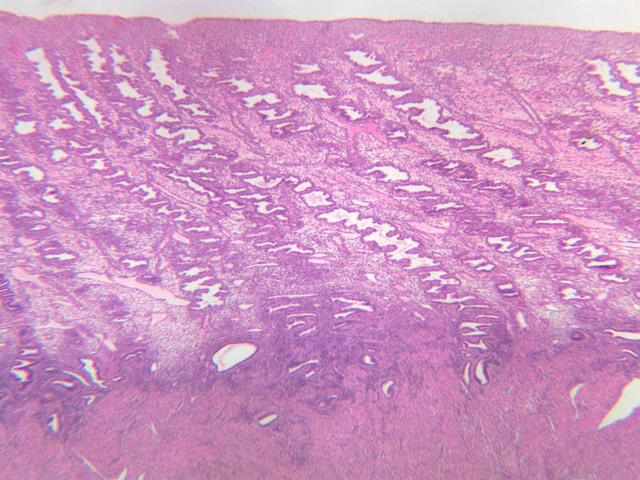

The wall of the uterine tube consists of three layers; a mucosa, a muscularis, and an adventitial/serous coat (B-96 [2.5x, 10x-labeled, 20x, 40x] [2.5x, 10x, 20x, 40x]; B-97, monkey uterus [2.5x, 10x, 20x, 40x]). The mucosa is organized into folds that vary in their degree of complexity with the tube regions. The mucosa is lined by a simple columnar epithelium consisting of two cell types, ciliated and non-ciliated, secretory (B-93 [10x, 20x, 40x-labeled]). The mucosal lamina propria consists of somewhat loose connective tissue and is highly vascular. No muscularis mucosae are present. The muscularis consists of two layers of smooth muscle, the inner being oriented in a circular fashion and the outer longitudinally.

The structure of the uterine tube is under the control of, and responds to, cyclic changes in the levels of steroid hormones. Structural alterations to provide favorable transport for the oocyte commence anew with the beginning of each cycle and peak at mid-cycle just before ovulation. These include increases in height and number of the ciliated cells as well as active secretion in the secretory cell. For the remainder of the cycle thereafter, dedifferentiation occurs. The cyclic changes occur to a greater extent in the upper ampulla and infundibulum. The margin of the infundibulum is drawn out into numerous finger-like processes called fimbrae. Microscopic examination of these will reveal that within the lamina propria are numerous large blood vessels, especially veins, as well as bundles of smooth muscle forming an intervening network. At the time of ovulation, the vessels become enlarged with blood, causing turgidity, which when combined with smooth muscle contraction brings the infundibular opening into close apposition with the ovarian surface.